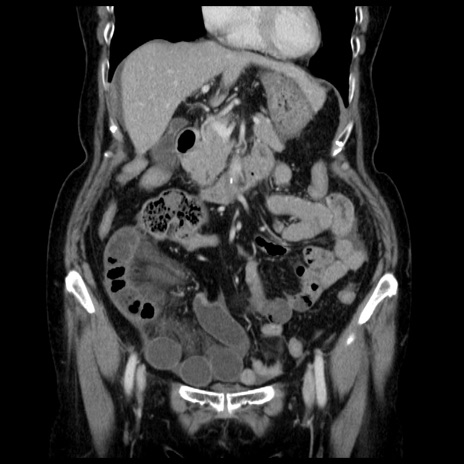

症例13(冠状断像)

【症例】70歳代女性

【主訴】腹痛、嘔吐

【現病歴】15時間程前(昨晩)より腹痛あり。今朝になっても症状の改善なく、嘔吐あり。腹痛も増悪あり、救急外来受診。

【既往歴】子宮癌全摘術後

【身体所見】意識清明、BP 121/72mmHg、P 74bpm、SpO2 100%(RA)、腹部:平坦・軟、腸雑音ほぼ聴取せず。下腹部・心窩部・臍左上に圧痛あり。反跳痛なし。

【データ】WBC 10600、CRP 0.15